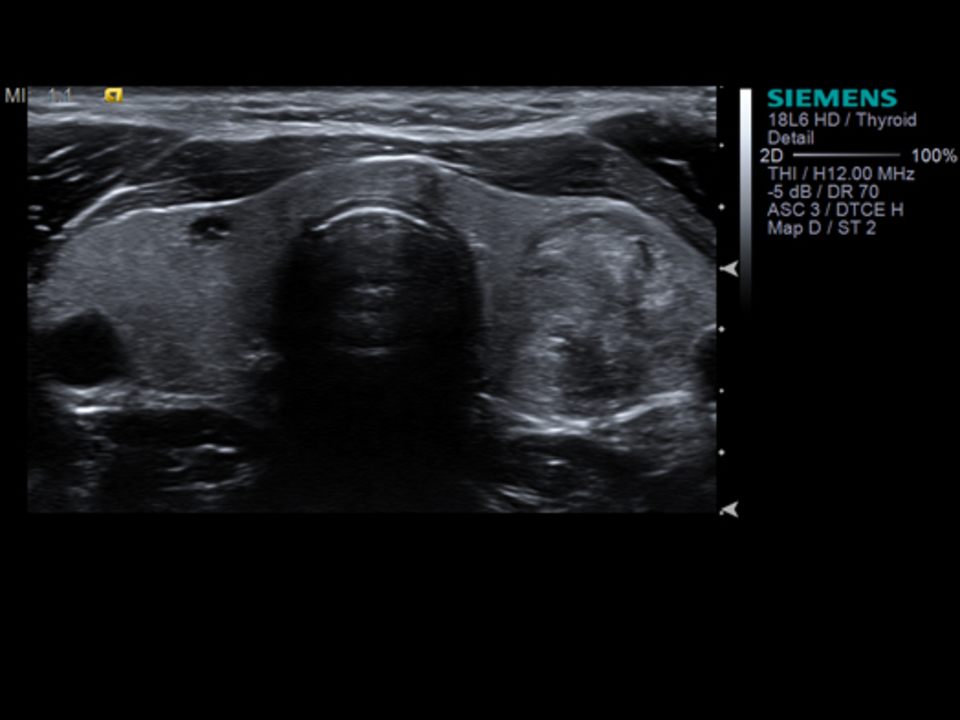

L'ecografia o ecotomografia è un sistema di indagine diagnostica medica che non utilizza radiazioni ionizzanti, ma ultrasuoni e si basa sul principio dell'emissione di eco e della trasmissione delle onde ultrasonore. Tale metodica viene considerata come esame di base o di filtro rispetto a tecniche di Imaging più complesse come TAC, imaging a risonanza magnetica, angiografia. Nelle mani del radiologo interventista è una metodica che può essere utilizzata per procedure terapeutiche mini invasive. L'ecografia è, in ogni caso, una procedura operatore-dipendente, poiché vengono richieste particolari doti di manualità e spirito di osservazione, oltre a cultura dell'immagine ed esperienza clinica. L'ecografia è una tecnica diagnostica che si serve degli ultrasuoni.

Può essere usato per esami quali; ecografia diagnostica, parti molli, tiroide, mammella, muscolo scheletrica, ecocolor dlopper, fibroscan, sonoelastografia